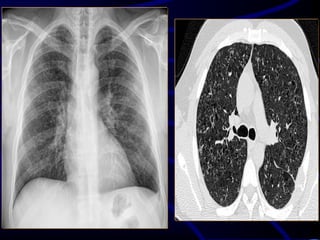

Case 5

A 68-year-old asymptomatic

nonsmoking woman underwent

preoperative screening chest

radiography in preparation for a total

knee arthroplasty. The radiographic

findings prompted subsequent chest

CT

Where is this lesion MOST

LIKELY located?

A. Lung parenchyma.

B. Mediastinum.

C. Pleura.

D. Chest wall..

What is the MOST LIKELY

diagnosis?

A. Primary lung cancer.

B. Chest wall chondrosarcoma.

C. Pseudotumor or vanishing

tumor of the pleura.

D. Localized fibrous tumor of the

pleura..

..pleura